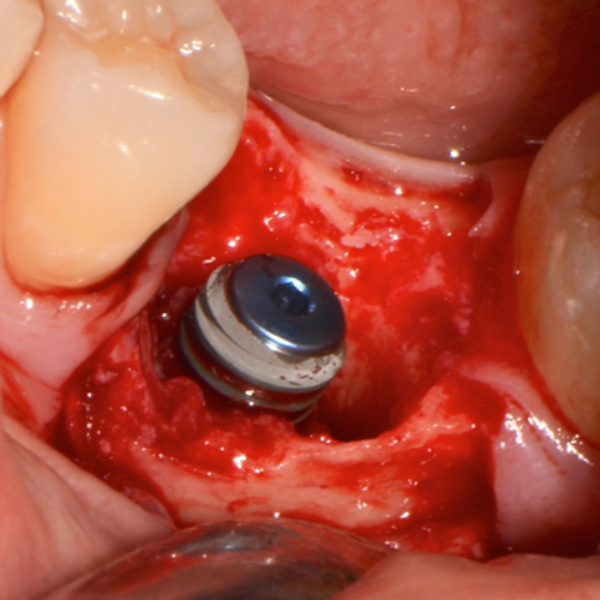

Immediate Dental Implant Placement

Tooth 14 slightly increased mobility, tenderness and bite pain. Suspected root fracture